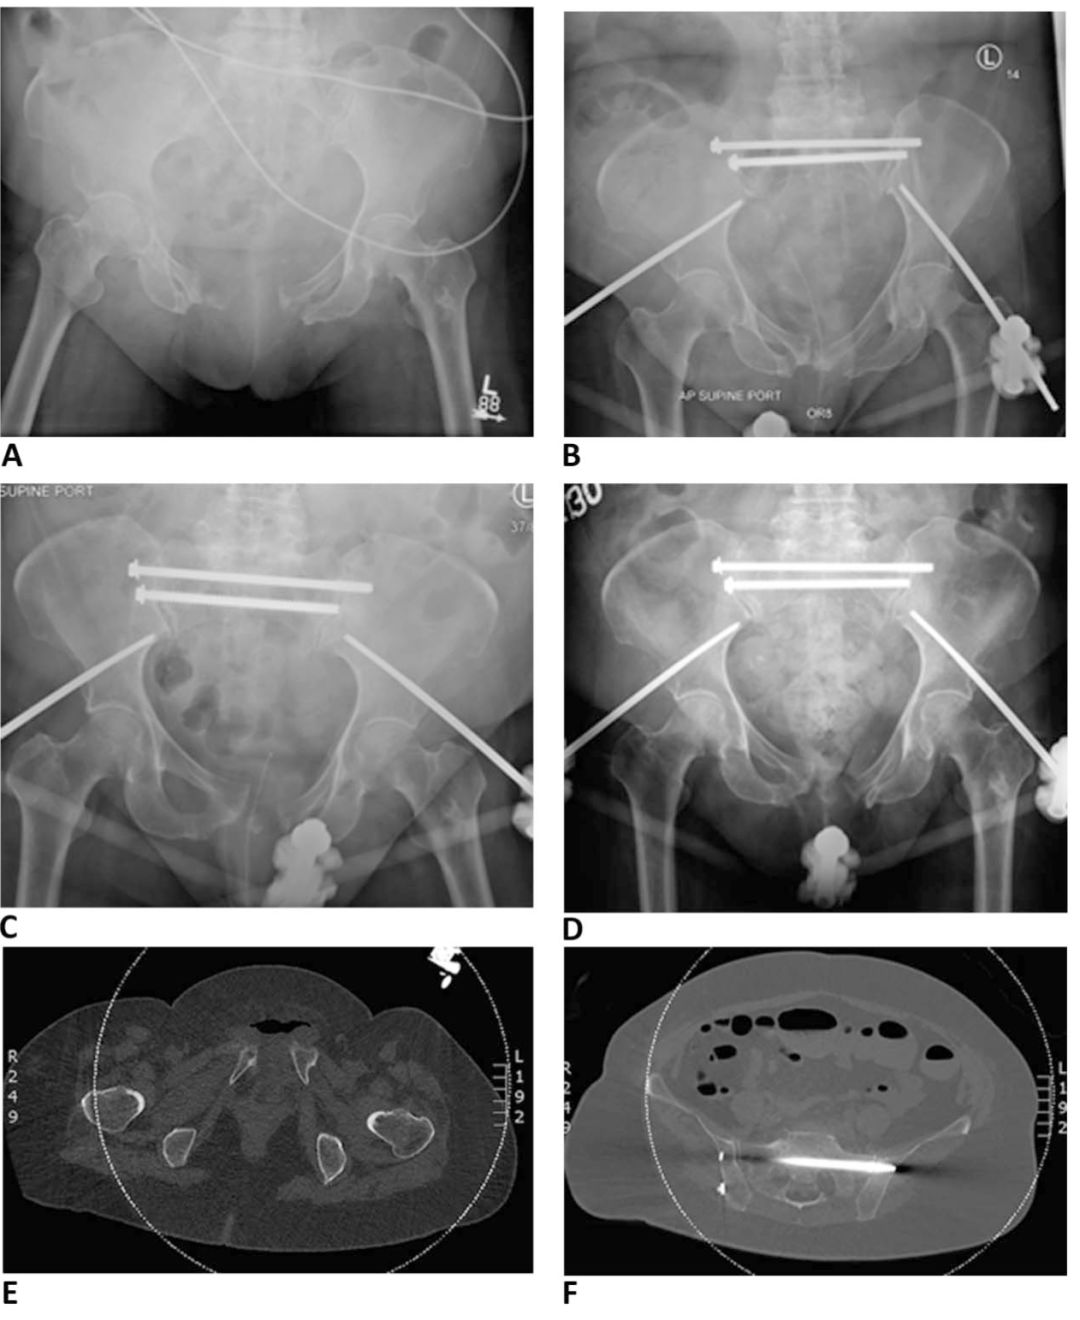

骨盆前环外固定术后最常见的并发症是钉道感染,发生率高达18%-50%。通常需要松解周围皮肤和反复换药处理。如果进展为蜂窝织炎或持续有渗出时需要抗生素治疗。持续感染会导致螺钉松动,根据感染情况,选择移除或更换螺钉固定。外固定架还可能会导致复位丢失(见图2)。外固定架治疗不稳定型骨盆前环损伤可能会导致畸形愈合。Dickson等研究报道了 “外固定架畸形” 的存在,并将其定义为:后环完全断裂的情况下,前方外固定架会引起屈曲、内旋畸形。

图2所示。A.68岁女性,车祸导致骨盆环前后挤压损伤(APC-II型),同时合并膀胱破裂。B.髋臼外固定架和S1/S2骶髂螺钉固定。C.术后1周显示前环复位丢失。D.术后6周,尽管后环复位,但前环逐渐复位消失。E.CT显示前环分离复位丢失。F.CT显示后环复位良好。